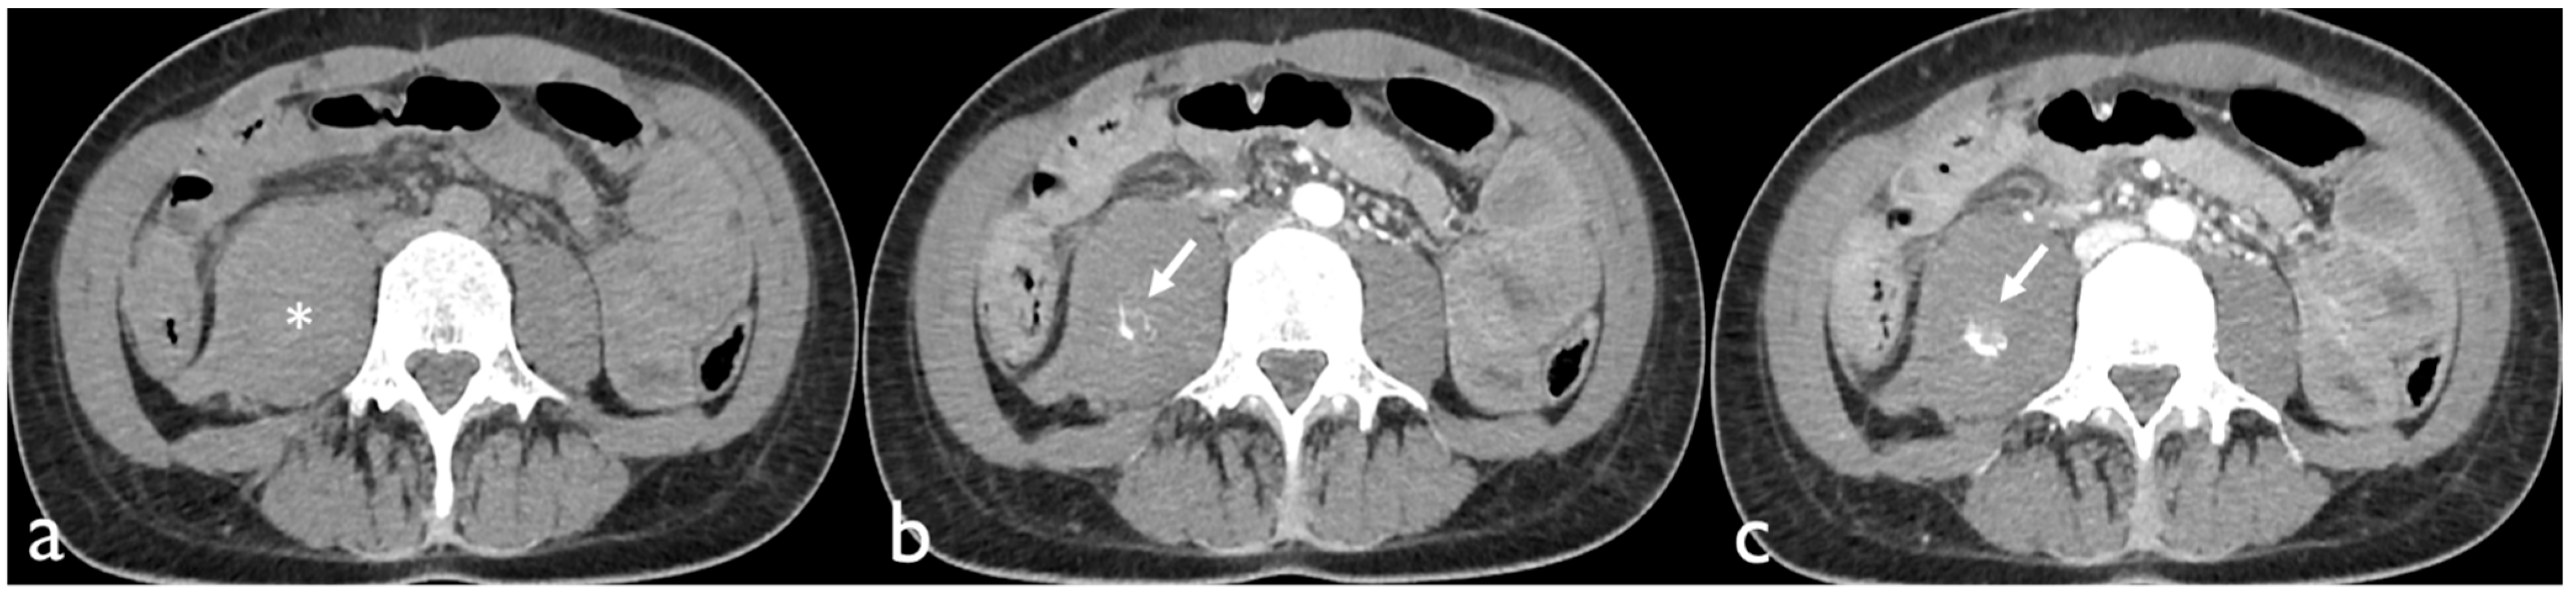

Technical success was obtained in 100% of patients in both groups. Clinical success rates were 70% for the COVID-19 group and 71% for the non-COVID-19 group; three out of 10 (30%) SARS-CoV-2-infected inpatients and four out of 14 (29%) patients without SARS-CoV-2 infection rebled after the first TAE (Figure 3). The Fisher exact test showed no statistical significance between the clinical success rates of retroperitoneal spontaneous hematoma embolization in patient with or without SARS-CoV-2 infection (Table 3).

Figure 3. Patient flowchart.